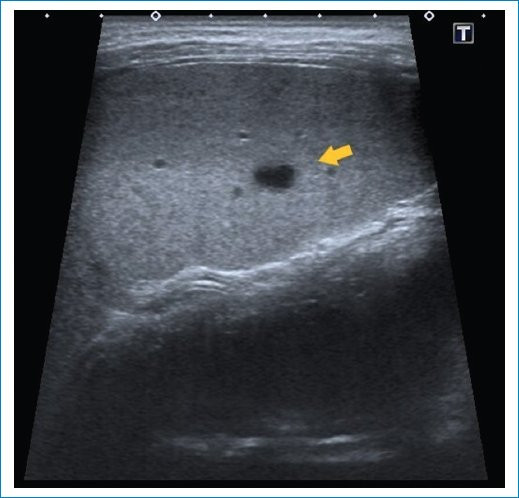

Se trata de una paciente de sexo femenino de 9 años, previamente sana, quien consultó al servicio de guardia pediátrica de nuestra institución por presentar síndrome febril prolongado de 12 días de evolución, sin otro síntoma asociado. A su ingreso, el examen físico reveló buen aspecto general. Se realizó una ecografía abdominal donde se evidenciaron lesiones redondeadas, hipoecoicas, de bordes regulares, que comprometían el parénquima hepático y esplénico (Figs. 1 y 2), las cuales fueron interpretadas como abscesos. Se complementó su estudio con tomografía computada (TC) de abdomen y pelvis con contraste endovenoso, siendo el hallazgo principal la presencia de múltiples imágenes hipodensas con morfología en racimos y realce en anillo tras la administración del contraste endovenoso, distribuidas en el parénquima hepático y esplénico, destacándose la mayor de 29 mm en segmento V hepático (Figs. 3 y 4). Debido a los hallazgos por imágenes y el estado clínico de la paciente, el primer diagnóstico que se planteó fue el de EAG. Se consideraron las lesiones hipodensas múltiples del hígado y bazo como una manifestación importante de enfermedad diseminada o atípica3,5,6. La madre confirmó un gato como mascota, lo cual estaba a favor de nuestra impresión diagnóstica.

Para realizar el diagnóstico de EAG se utilizan pruebas serológicas que detectan la presencia de anticuerpos contra B. henselae4,8. A nuestra paciente se le realizaron pruebas de anticuerpos B. henselae IGG e IGM cuyo resultado fue positivo (1/1.280). Los estudios de imágenes poco aportan ante cuadros de EAG típico, podemos encontrar en la evaluación ecográfica ganglios linfáticos aumentados de tamaño con pérdida de su ecoestructura habitual, generalmente con necrosis central y asociados a edema circundante. Sin embargo, en pacientes con enfermedad atípica o diseminada se han asociado hallazgos característicos que pueden ser útiles para establecer el diagnóstico como la formación de múltiples granulomas hepáticos y esplénicos, con o sin hepatoesplenomegalia, identificados mediante ecografía y TC3. Estos granulomas se identifican inicialmente como lesiones hipoecoicas en ecografía, y en algunos casos presencia de calcificaciones en las fases tardías. En TC presentan características similares a cualquier absceso, hipodensos, redondeados o con morfología en racimos y tras la administración del contraste pueden permanecer hipodensos o mostrar un realce periférico característico. La multiplicidad y el compromiso de varios órganos se relacionan más con infecciones bacterianas, a diferencia de las de origen parasitario, lo cual nos orienta a un mejor diagnóstico.